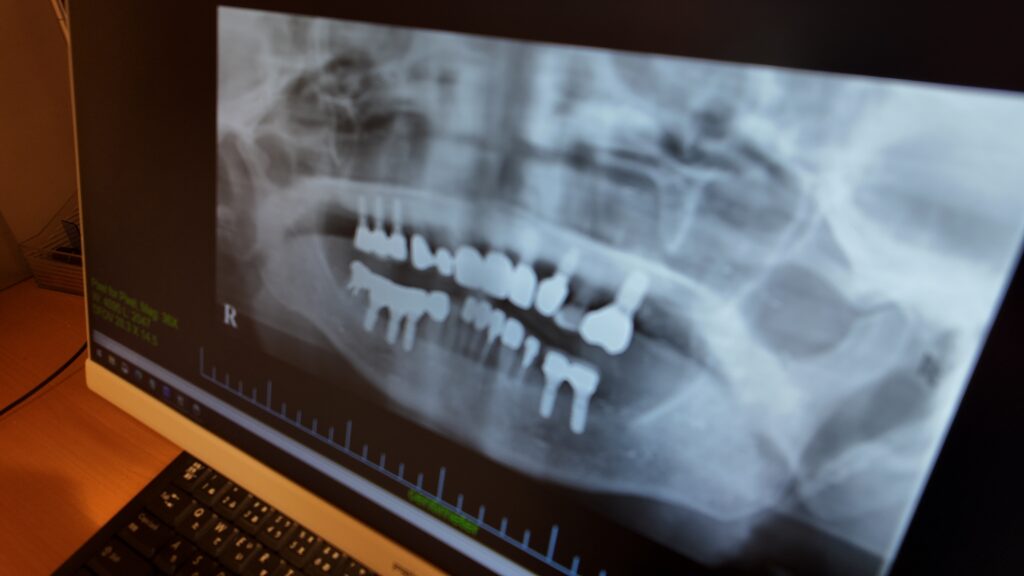

02|レントゲン撮影

現在の状況を正確に把握するため、

顎骨の状態や神経の位置を確認します。

※撮影により治療の安全性と精度が向上します。